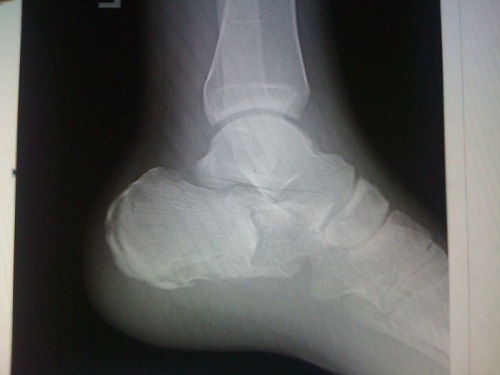

Выявить данный вид повреждения довольно сложно. Именно поэтому без обследования травматологом и без рентгенологического исследования здесь просто не обойтись. Некоторые считают, что такая «мелкая» травма заживёт сам по себе и ничего здесь предпринимать не нужно. Но это далеко не так. Даже если такой перелом и заживёт, то он оставляет после себя много негативных последствий, вплоть до того, что человек не может нормально опираться на повреждённую ногу при ходьбе.

Хороший результат даёт такой метод лечения, как скелетное вытяжение. Но он требует некоторых навыков от самого врача, правильного подбора груза и тщательного контроля за состоянием поврежденного места. А для этого необходимо регулярно проводить контрольное рентгенологическое исследование, по результатам которого будет понятно, как проходит заживление.